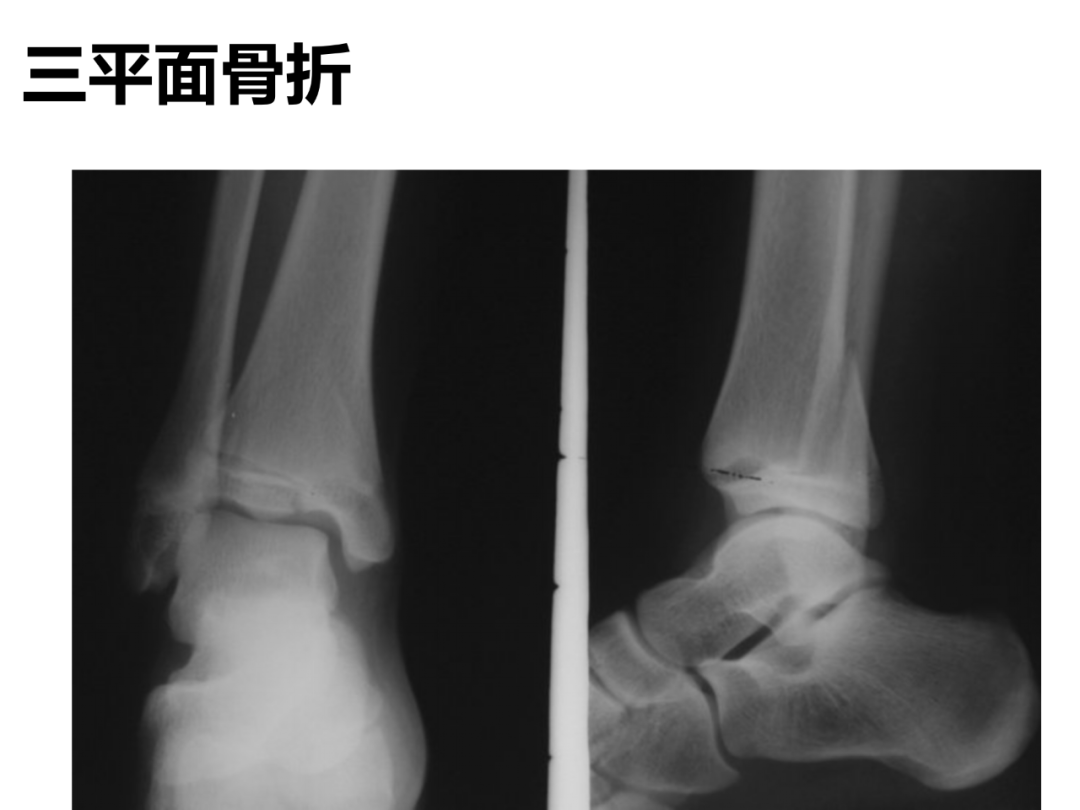

小儿骨科X线片汇总,临床读片宝典!